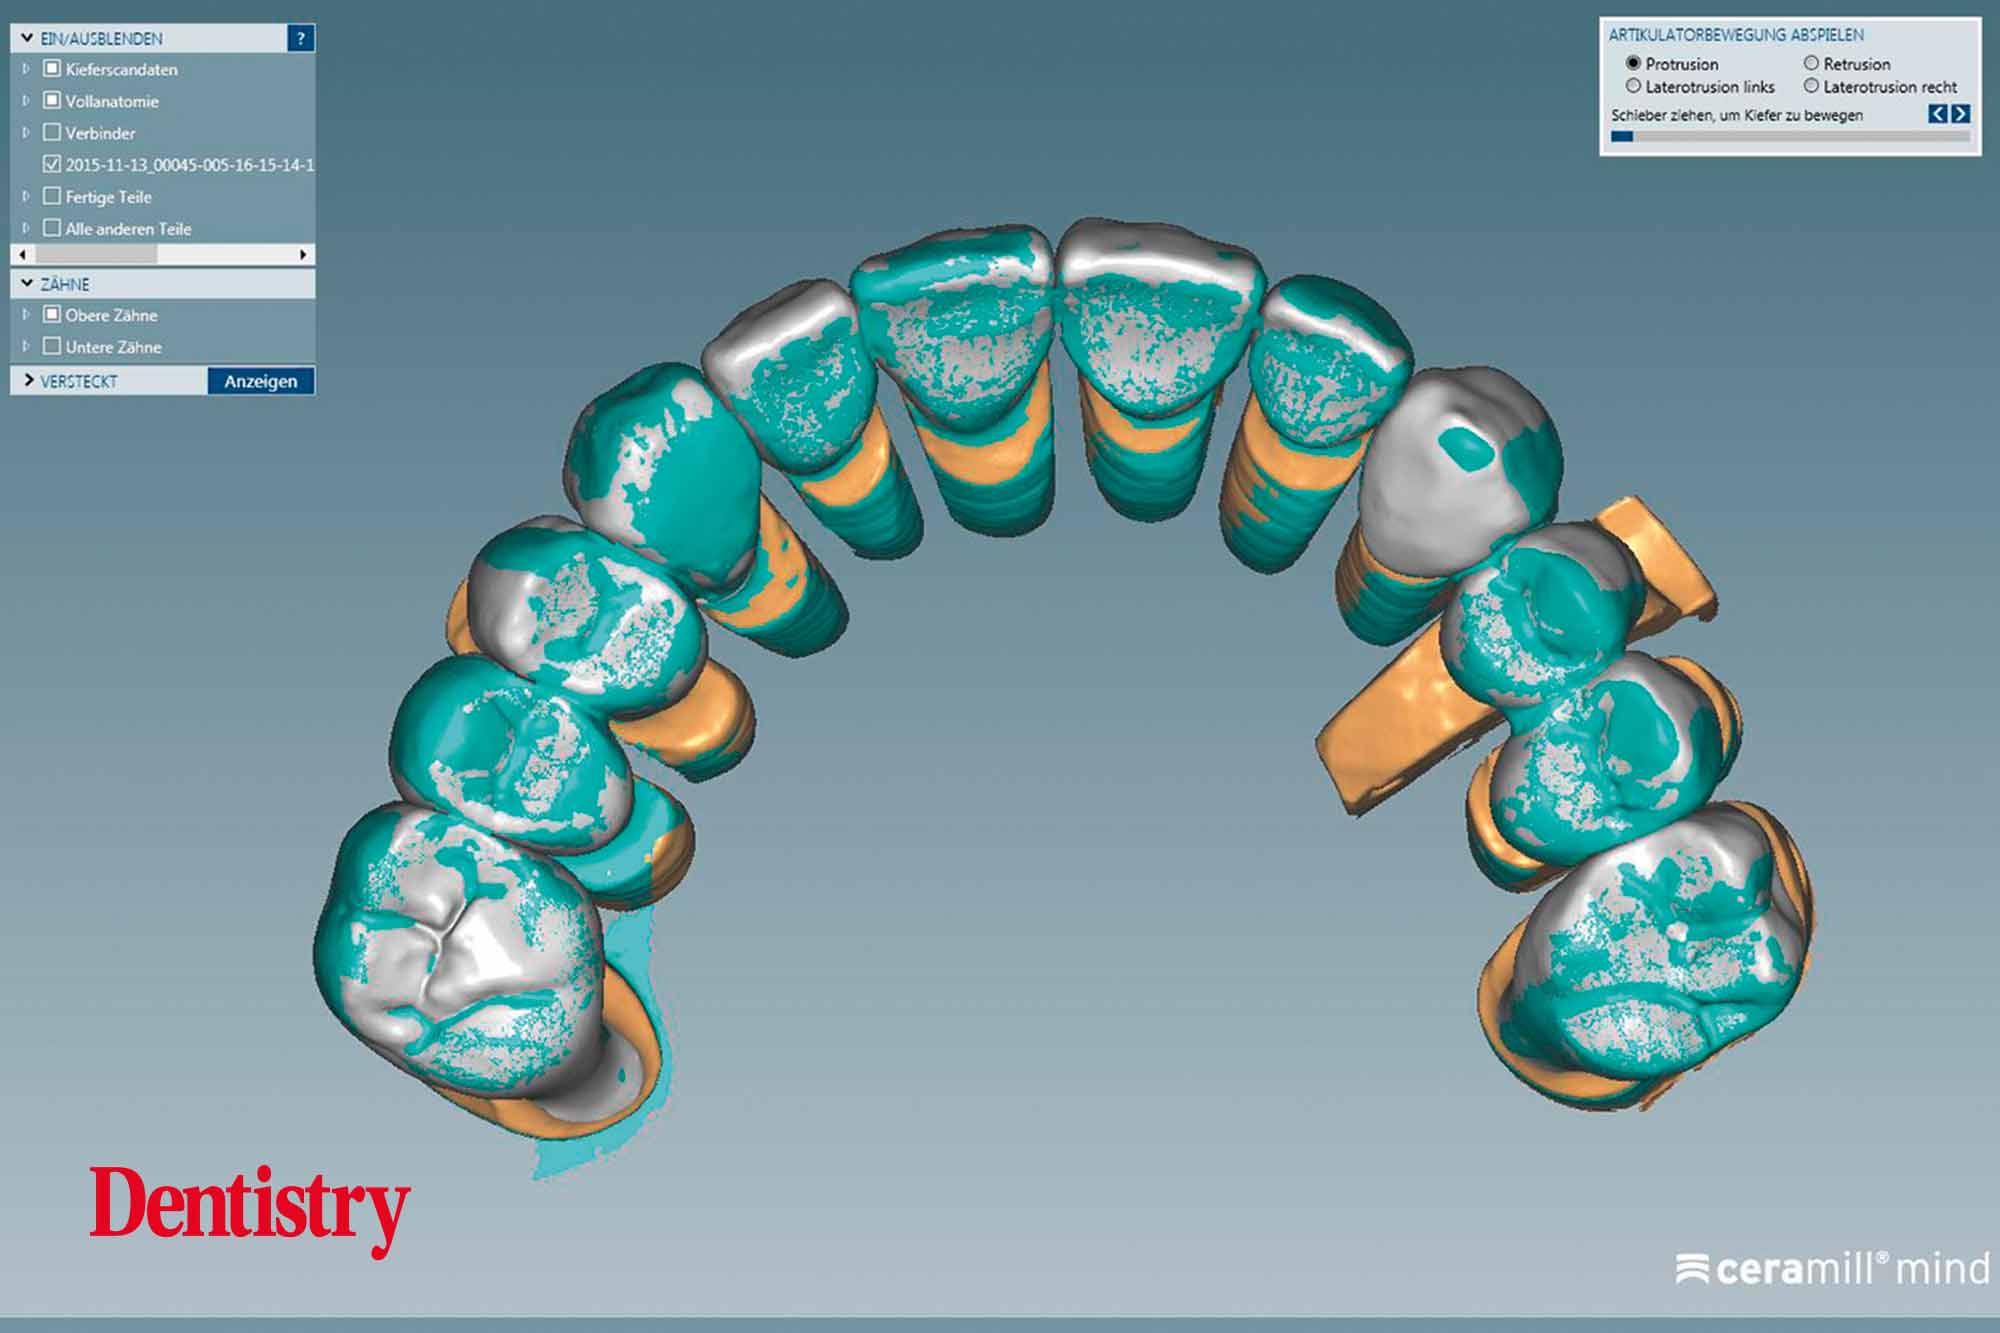

CAD design of the final crowns

Using the CAD software (Figure 12), we were able to round off and refine the areas on the temporary crowns that had been ground and modified intraorally. As a result, this left the remaining areas unchanged.

Canine guidance with a light group function was created on the Ceramill Mind Wizard.